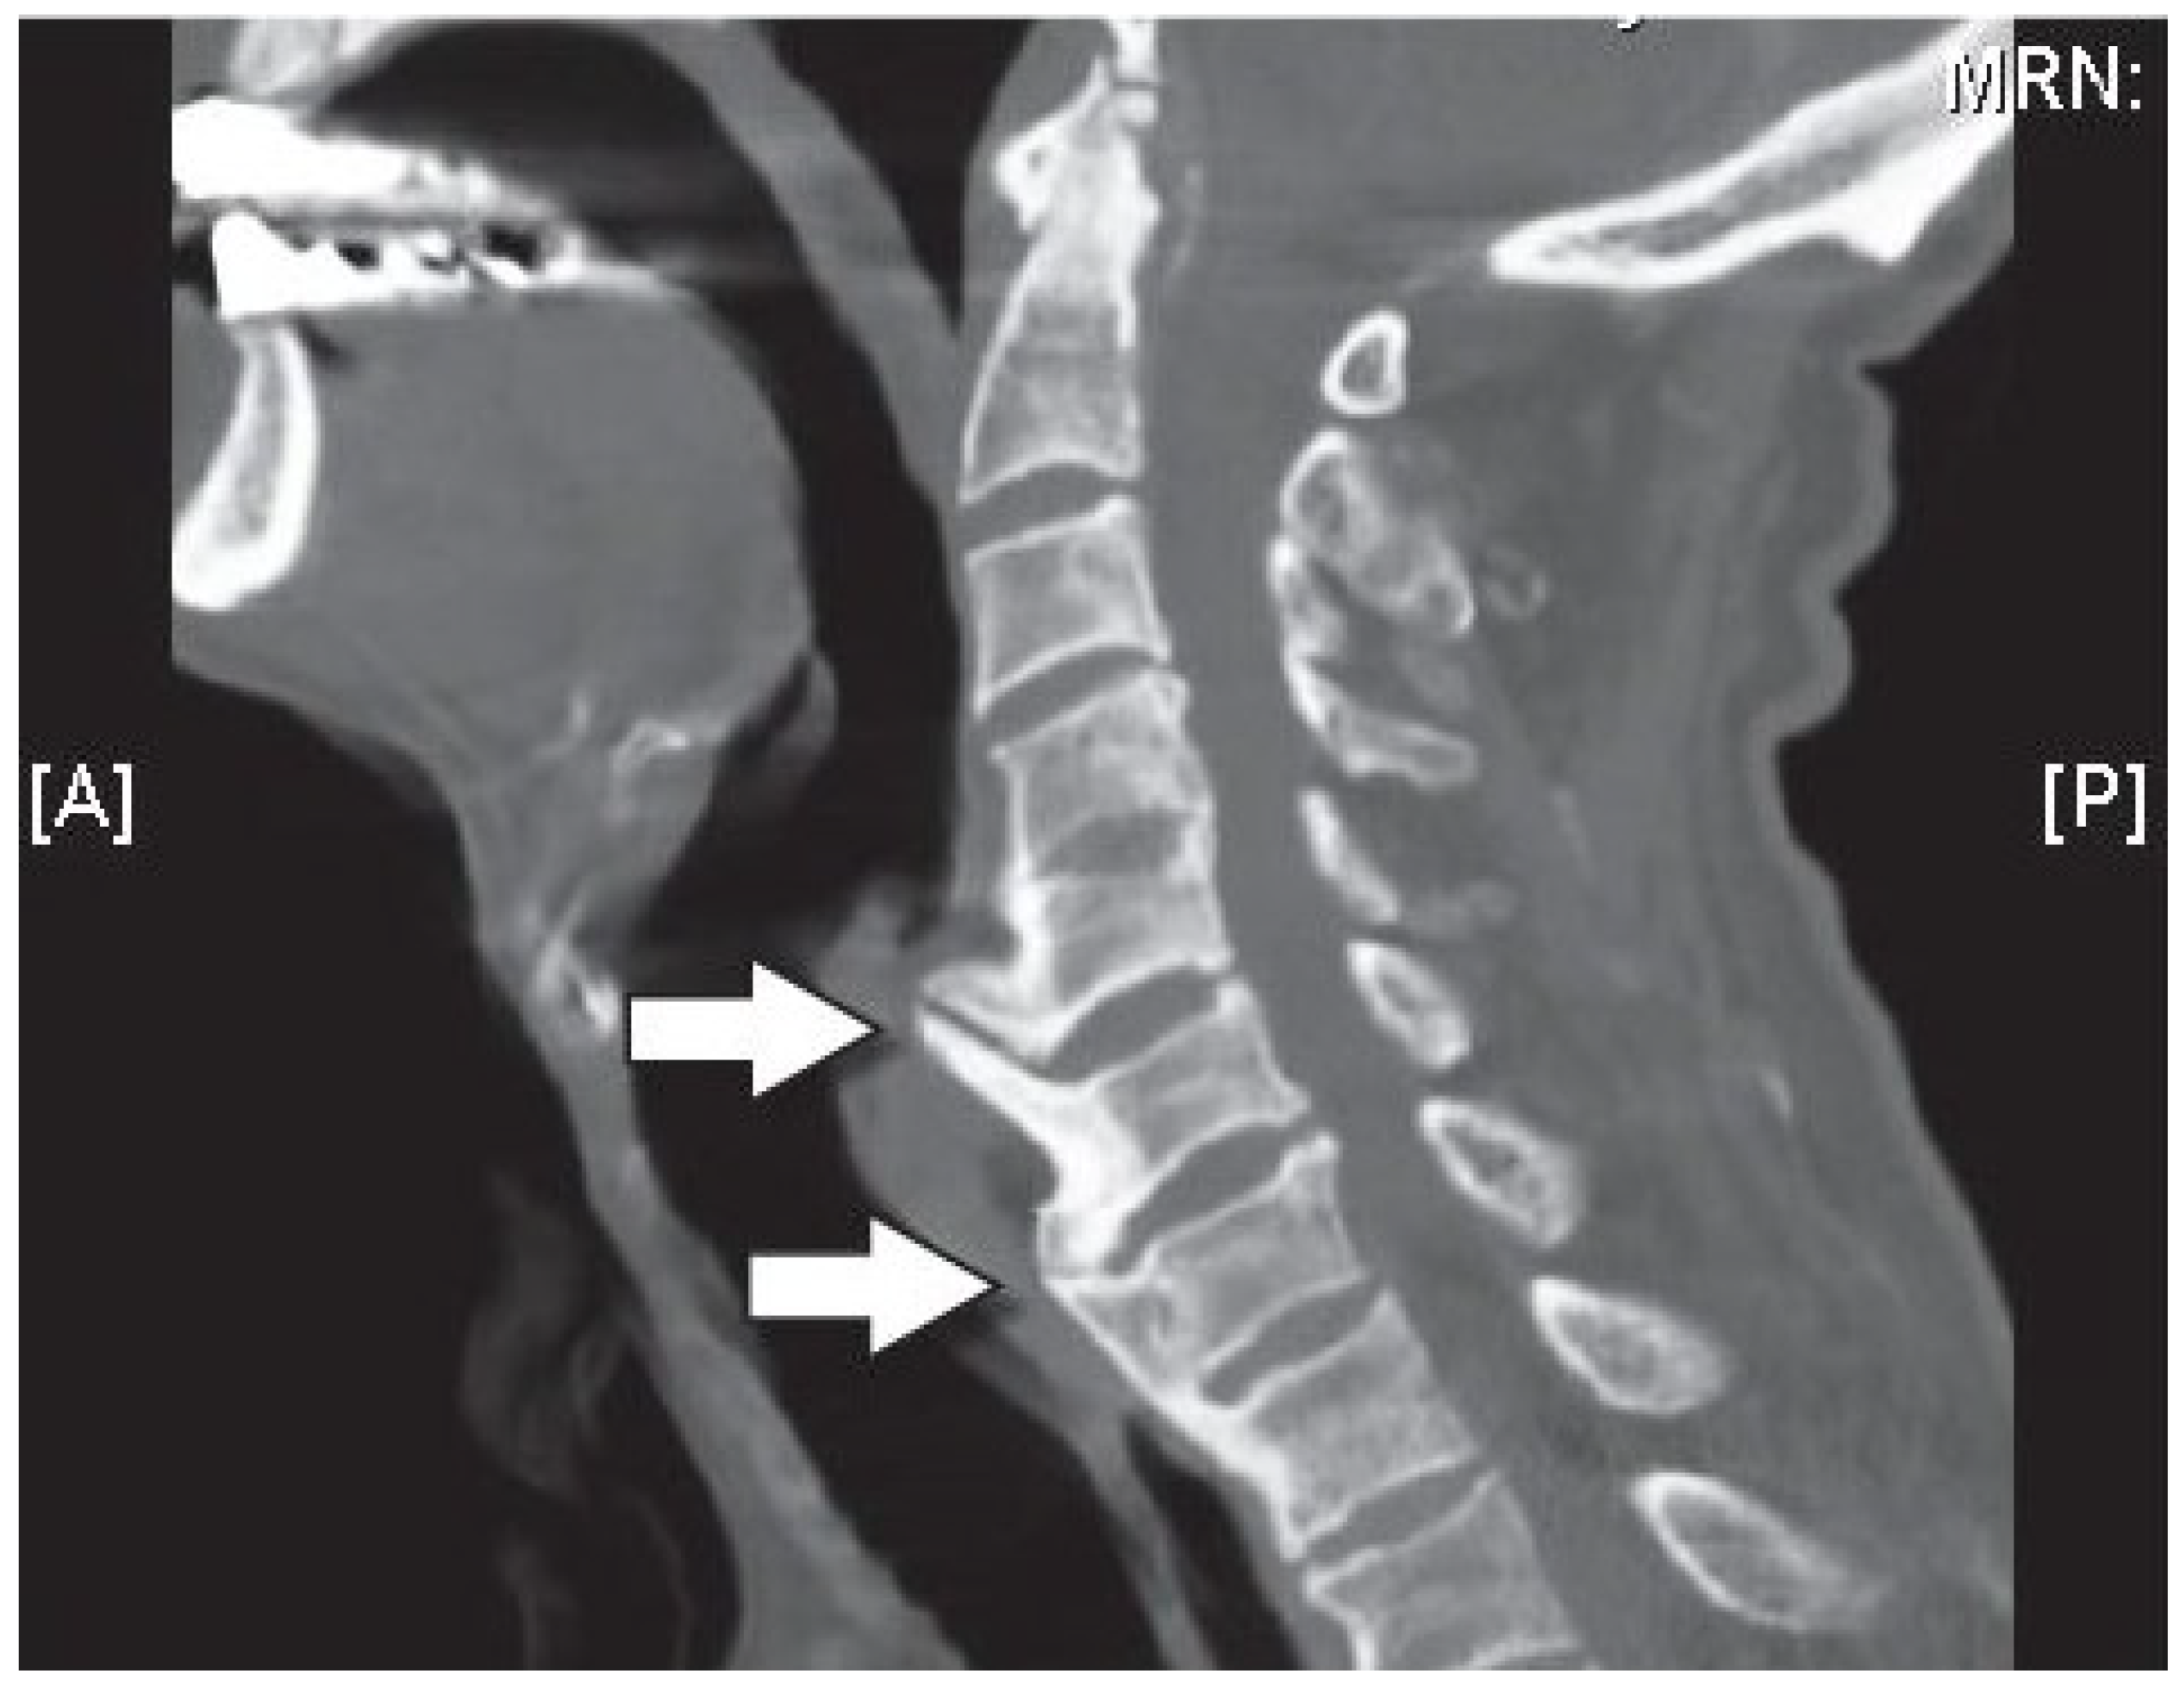

3.4. Disc Herniation (Prolapse/Rupture)

- Yeung, J.T.; Johnson, J.I.; Karim, A.S. Cervical disc herniation presenting with neck pain and contralateral symptoms: A case report. J. Med. Case Rep. 2012, 6, 166. [Google Scholar] [CrossRef] [PubMed]